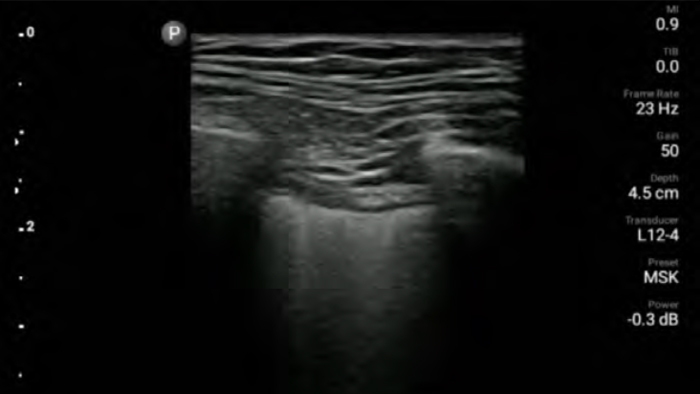

Lumify handheld ultrasound for anesthesiology helps you clearly visualize border definition with your needle placement, surrounding nerves, vessels and fascial planes.

Lumify helps you clearly visualize needle placement, surrounding nerves, vessels and fascial planes.

Lumify L12-4 broadband linear array transducer

• 12 to 4 MHz extended operating frequency range

• Aperture size: 34mm

• 2D, steerable color Doppler, M-mode, advancedXRES and multivariate harmonic imaging, SonoCT

• High resolution imaging for shallow applications: soft tissue, vascular, superficial, musculoskeletal and lung

• Center line marker

• USB-C transducer with replaceable cable